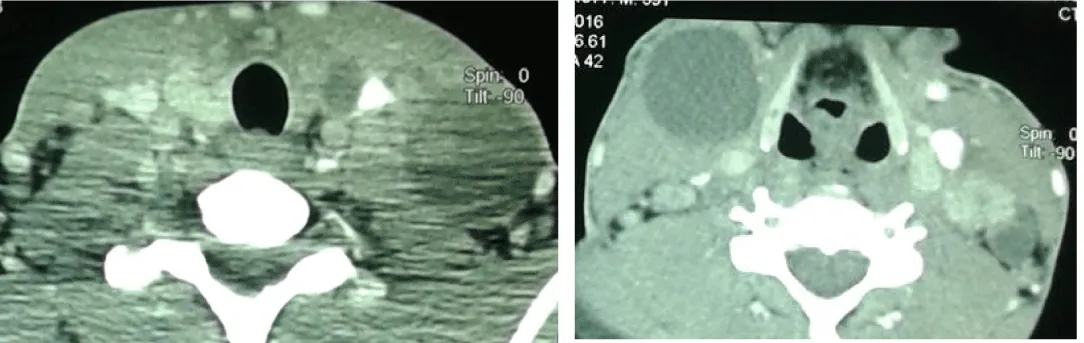

Cervical CT scan showed two large cystic cervical lymph nodes, the left located being larger than the right one and the thyroid gland had multiple hypodense nodules (Figure 2).